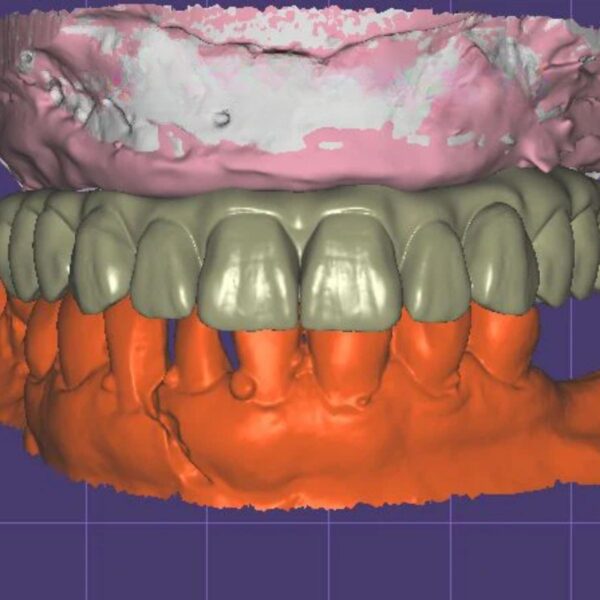

Screw-Retained Implant Crown Design Service (ASC Ready)

- ✓ ASC Technology: Angulated Screw Channels (up to 25°) to hide access holes.

- ✓ Passive Fit: Perfect cement gap settings for Ti-Base bonding.

- ✓ Tissue Health: Custom emergence profile to shape the gingiva.

Compatible with: Nobel, Straumann, Zimmer, BioHorizons, etc.